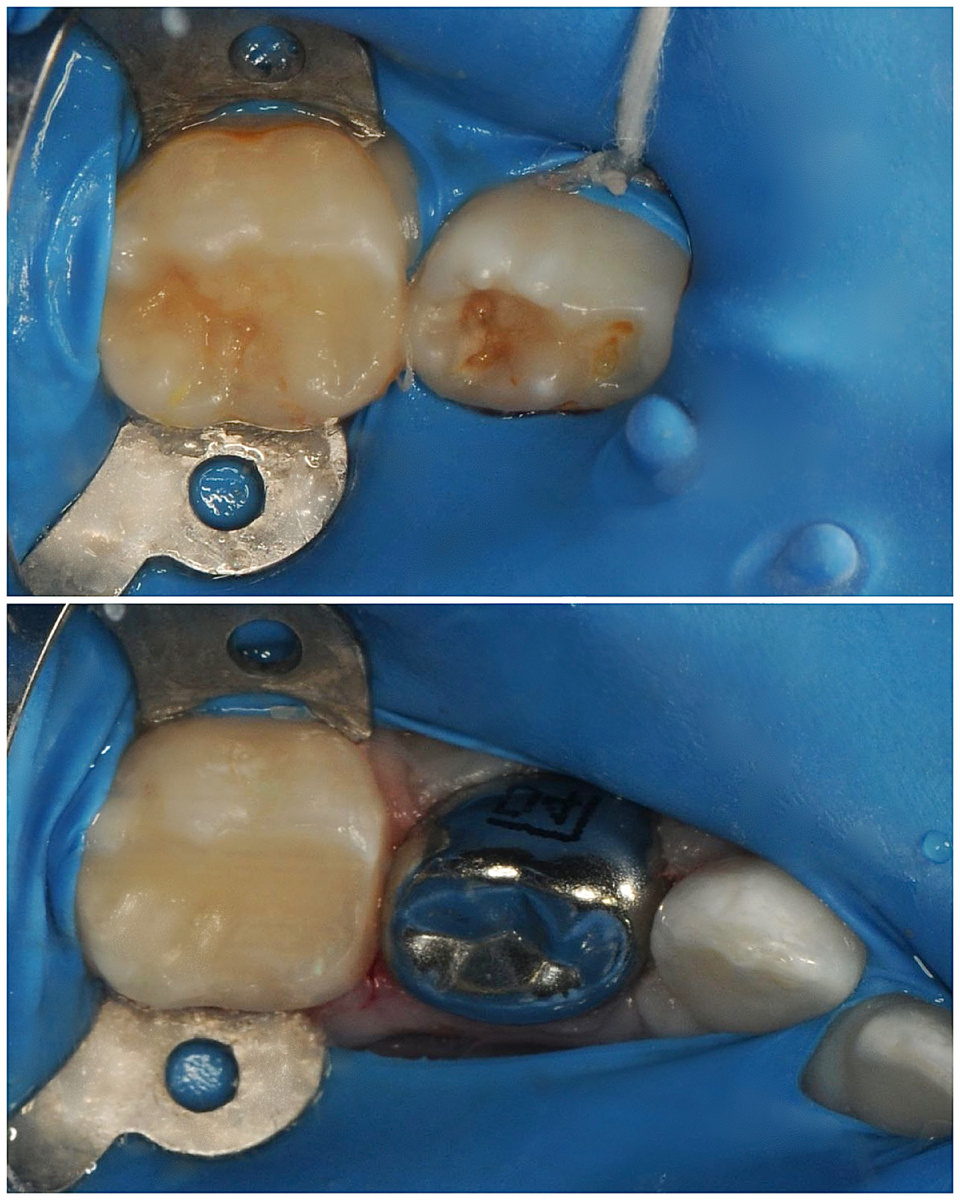

🔍 При тщательной диагностике зубов мы выявили серьёзную проблему: сразу 14 молочных зубов нуждались в лечении. Это был обширный множественный кариес у ребёнка 3 лет, а один зуб – с диагнозом пульпит молочного зуба.

🔹 Вылечили 13 зубов с кариесом

🔹 Провели лечение 1 зуба с диагнозом пульпит и восстановили его металлической коронкой

🔹 И всё это – без стресса и дискомфорта для ребёнка! Возраст пациента 3 года.